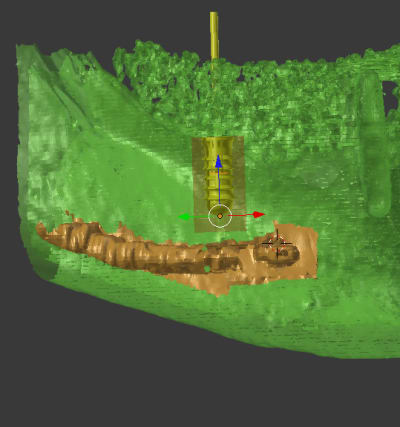

pluton je pense avoir trouver comment mettre en évidence le NAI

c'est pour mon prochain cas

salut est ce plus visible en vert/bleu

je l'ai repéré à droite et pas à gauche

pas de souci blender peut tout faire

implant léone 4.1x10 posé au hasard pour la photo

en ombré rouge la protection 2mm pour le NDI et 1.25mm sur les cotés

est ce que c'est plus lisible en vert?